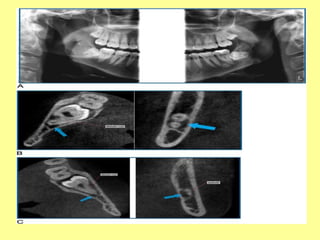

6)Partial Odontectomy

• If the roots lie in intimate contact with the IAC, a

partial odontectomy (coronectomy) should be

considered.

• The roots left in situ may remain in place and

rarely, if ever, cause infection or other untoward

incident .

• In some cases, the roots migrate in a superior

direction away from the IAC, allowing their

subsequent removal to be nonproblematic.

(A)Preoperative view of distoangular M3 lying adjacent to IAC.

(B)Immediate postoperative film showing removal of M3 crown;

roots left in situ to avoid injury to IAN.

(C) After 5 years, regeneration

of bone and no reaction around retained M3 roots are noticed.

(A)When the M3must be sectioned using a high-speed drill, carry the bur only three-fourth of the way through the tooth structure before separating the crown or the roots with an elevator. (B) The IAC (arrows) often lurks just beneath a deeply imbedded horizontally affected M3. 5)Sectioning Teeth

6)Partial Odontectomy • Ifthe roots lie in intimate contact with the IAC, a partial odontectomy (coronectomy) should be considered. • The roots left in situ may remain in place and rarely, if ever, cause infection or other untoward incident . • In some cases, the roots migrate in a superior direction away from the IAC, allowing their subsequent removal to be nonproblematic.

(A)Preoperative view ofdistoangular M3 lying adjacent to IAC. (B)Immediate postoperative film showing removal of M3 crown; roots left in situ to avoid injury to IAN. (C) After 5 years, regeneration of bone and no reaction around retained M3 roots are noticed.